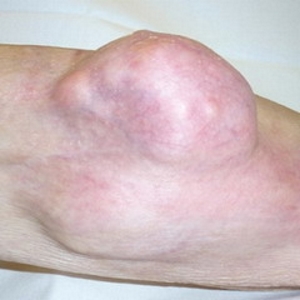

Увеличивающаяся опухоль может нарушать функционирование крупных кровеносных сосудов в области коленного сустава, что приводит к сильному отеку мягких тканей ниже колена и образованию участков некроза. На поздних стадиях саркома прорастает в соседние ткани, включая мышцы и костномозговой канал. Метастазы могут обнаруживаться в почках, печени, мозге и других органах.

Растущая опухоль